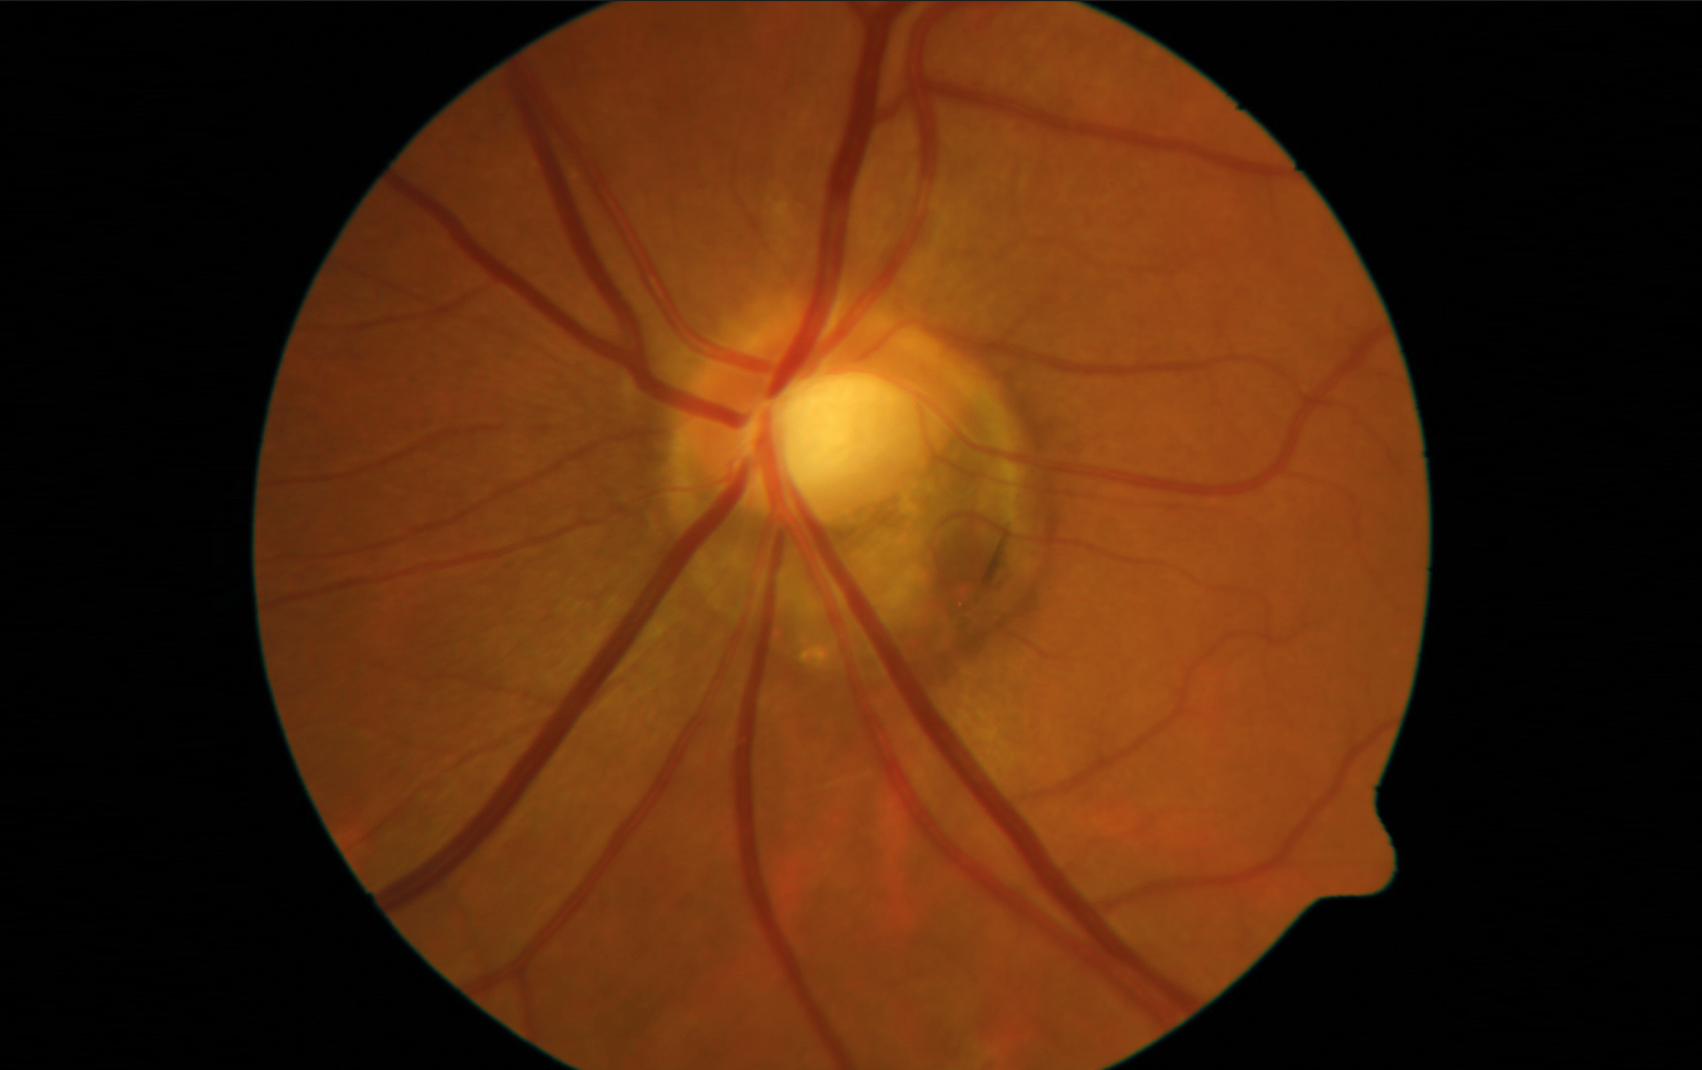

Figure 2. Patiente de 26 ans présentant une baisse d’acuité visuelle avec un décollement séreux rétinien hémorragique visible à l’OCT (A, tête de flèche). Les temps tardifs de l’angiographie à la fluorescéine ne montrent aucune diffusion (B) et la rupture de la membrane de Bruch est hypofluorescente sur le temps tardif de l’angiographie au vert d’indocyanine (C). L’OCT-A segmentée sur la rétine externe ne montre aucun signal vasculaire (D).